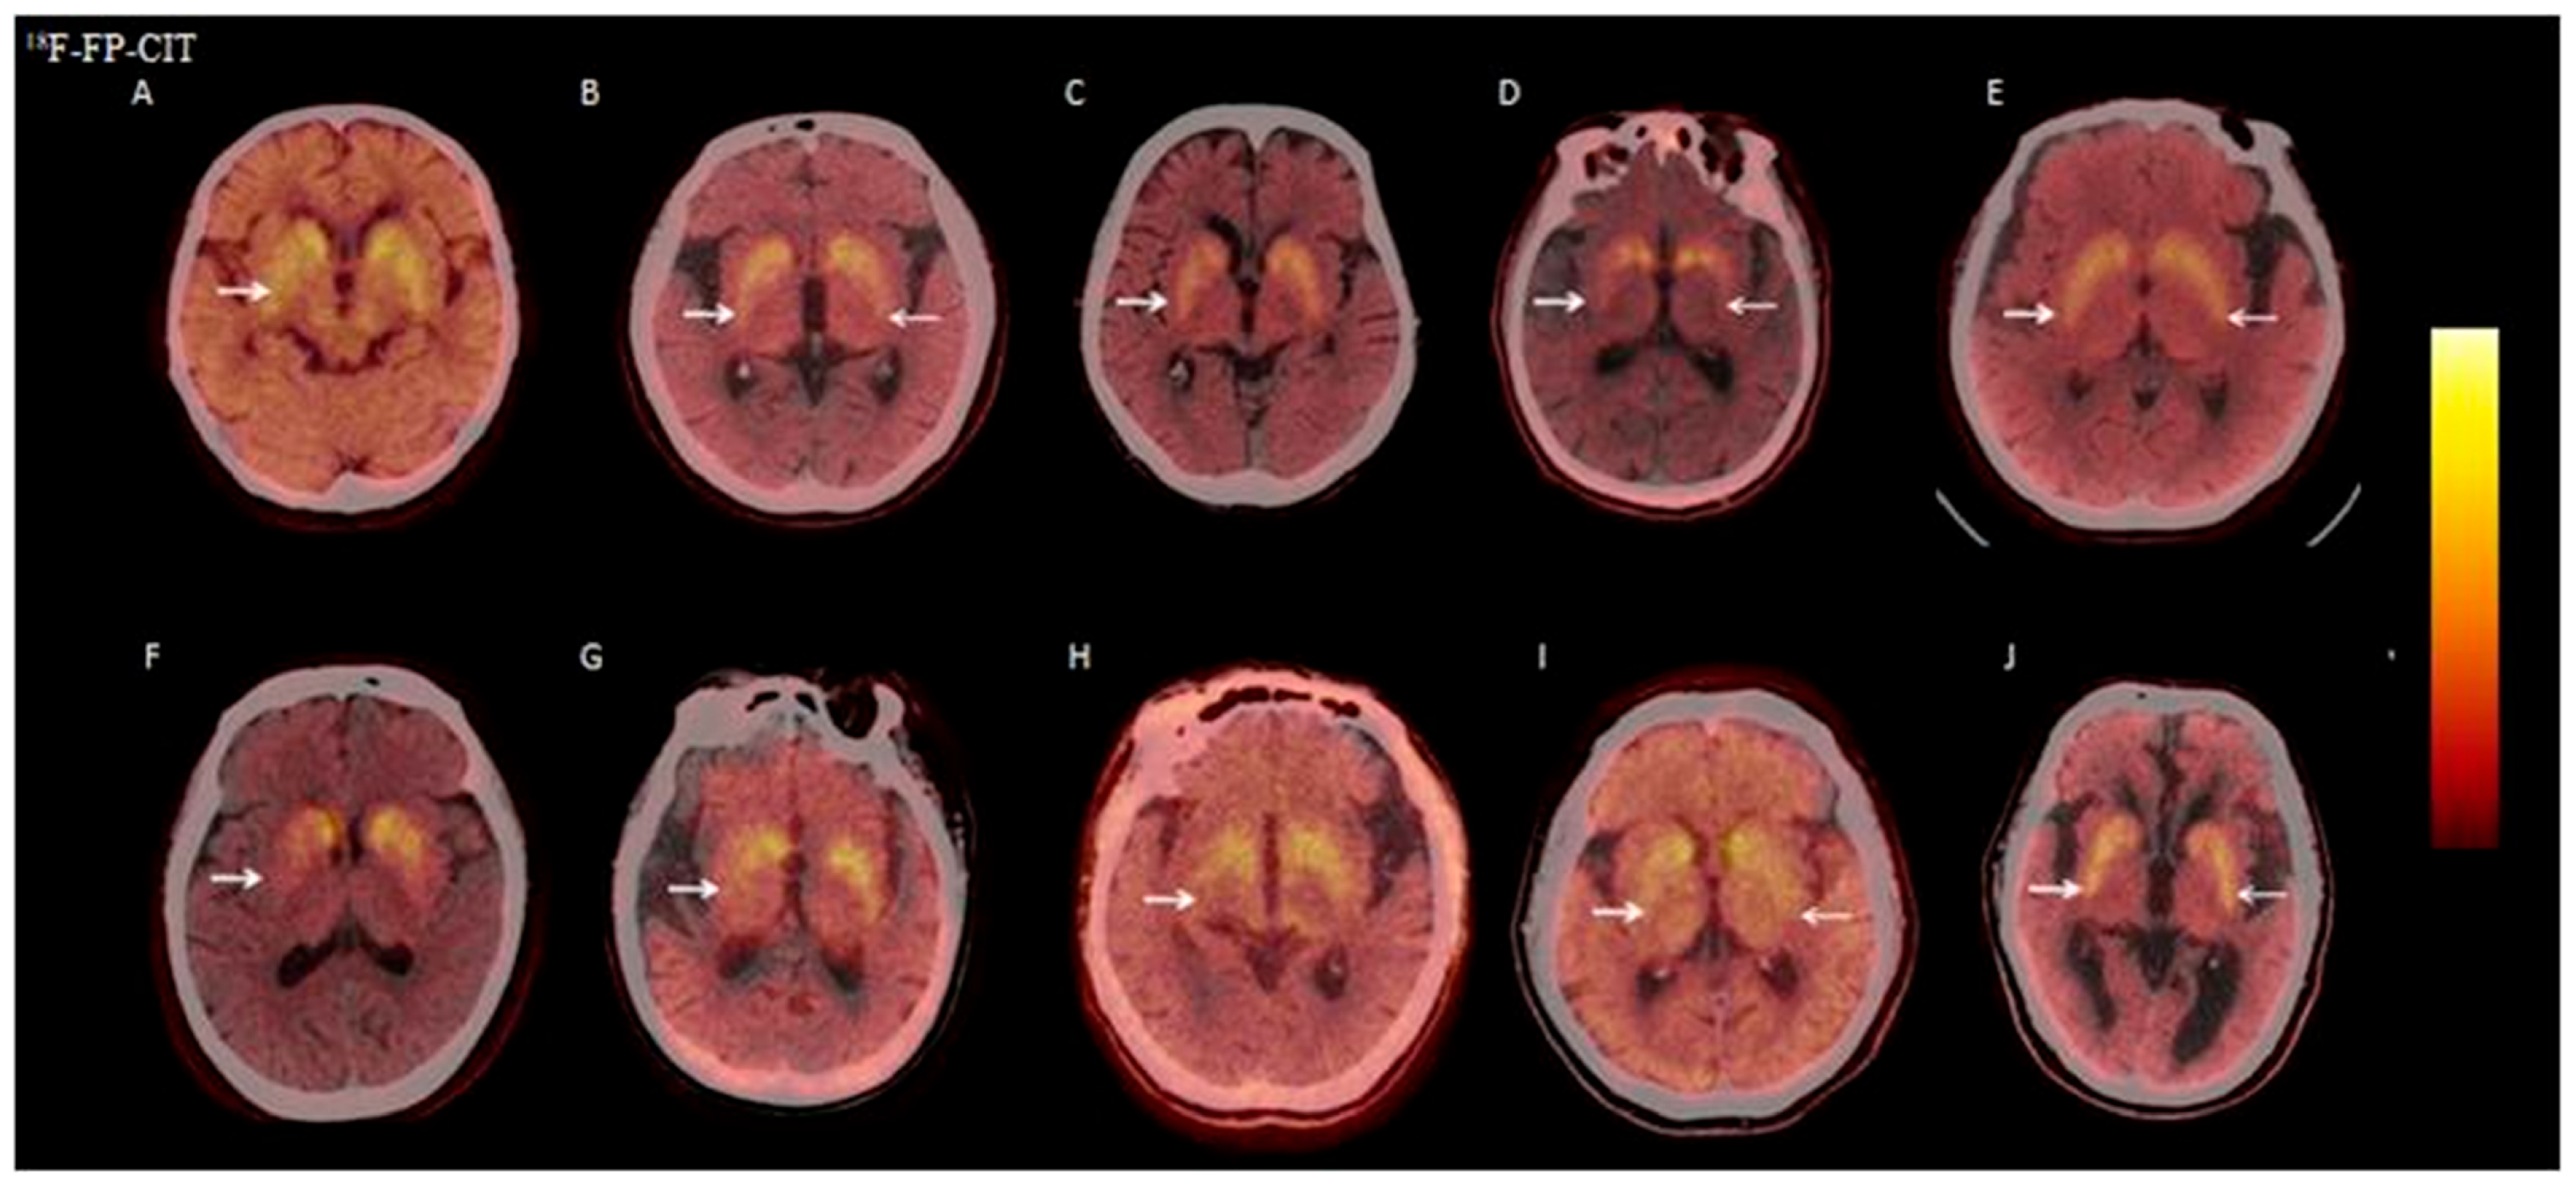

3.2.6. Visual Analysis of 18F-FP-CIT PET/CT